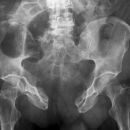

Fraktur Ramus pubis sup. und inf.